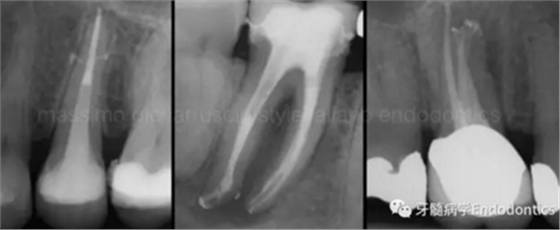

圖1.探查冠方2/3可以獲得有關(guān)根管系統(tǒng)解剖形態(tài)的相關(guān)信息,獲得根管彎曲和多重彎曲程度,或者是否存在根管彎曲的一些重要反饋。醫(yī)生需要重視五種可能遇到的根管解剖類型(包括融合、彎曲、多重彎曲、分歧、分支)。

當(dāng)建立直線通路、找到所有的根管口后,重心應(yīng)轉(zhuǎn)移到根管預(yù)備上。若牙髓存在活力且持續(xù)滲血,應(yīng)使髓室內(nèi)充滿粘性螯合劑。在牙髓已壞死的情況下,應(yīng)使用加熱的5.25%次氯酸鈉溶液沖洗并徹底充滿髓室。探查前,根據(jù)術(shù)前X線片測量并預(yù)彎小的不銹鋼銼,以順應(yīng)預(yù)估的根管長度及彎曲度。使用0.02錐度的10號不銹鋼手用K銼探查根管冠方2/3。